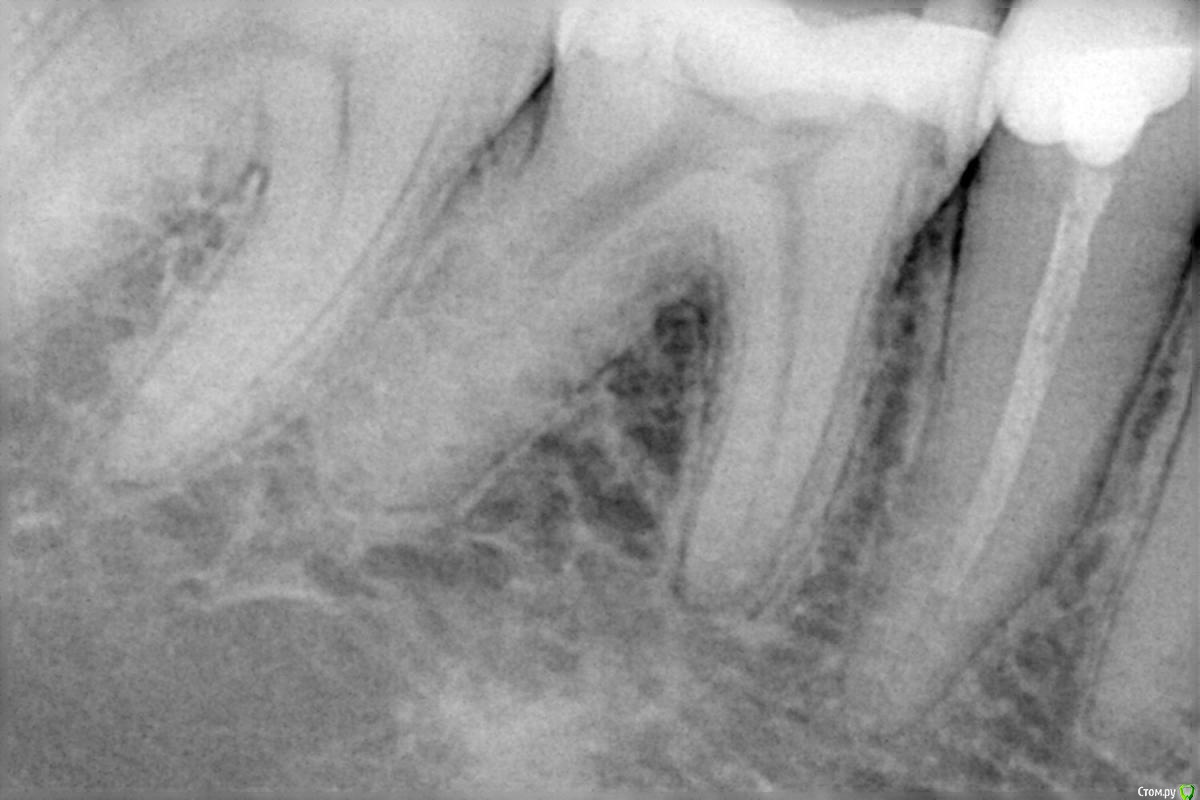

KatKy Опубликовано 25 октября, 2015 Поделиться Опубликовано 25 октября, 2015 (изменено) Здравствуйте, помогите пожалуйста, т.к. сил больше нет.Болит 6-ка справа, один врач говорит удалять, второй сказал, что сохраним и пролечил каналы(3 месяца назад), боль(ноющая) не ушла болит так же при надавливании.Снимок прилагаюНедел уже пью найз и амоксицилин Изменено 25 октября, 2015 пользователем KatKy Ссылка на комментарий

KatKy Опубликовано 25 октября, 2015 Автор Поделиться Опубликовано 25 октября, 2015 К сожалению нет сейчас денег на КТЕсть снимок до пломбировки каналовСтоматолог говорит, что это постпломбировачные боли...спустя 3 месяца Ссылка на комментарий

KatKy Опубликовано 25 октября, 2015 Автор Поделиться Опубликовано 25 октября, 2015 (изменено) Нет после пломбировки контрольный рентген не делали, стоматолог сказал не нужноА на что вообще похоже? Что может болеть, я не понимаю есть там воспаление или нет Есть вот такой рентген, на фотоаппарат сама сфоталаА по ОТПГ совсем ничего не видно? Изменено 25 октября, 2015 пользователем KatKy Ссылка на комментарий